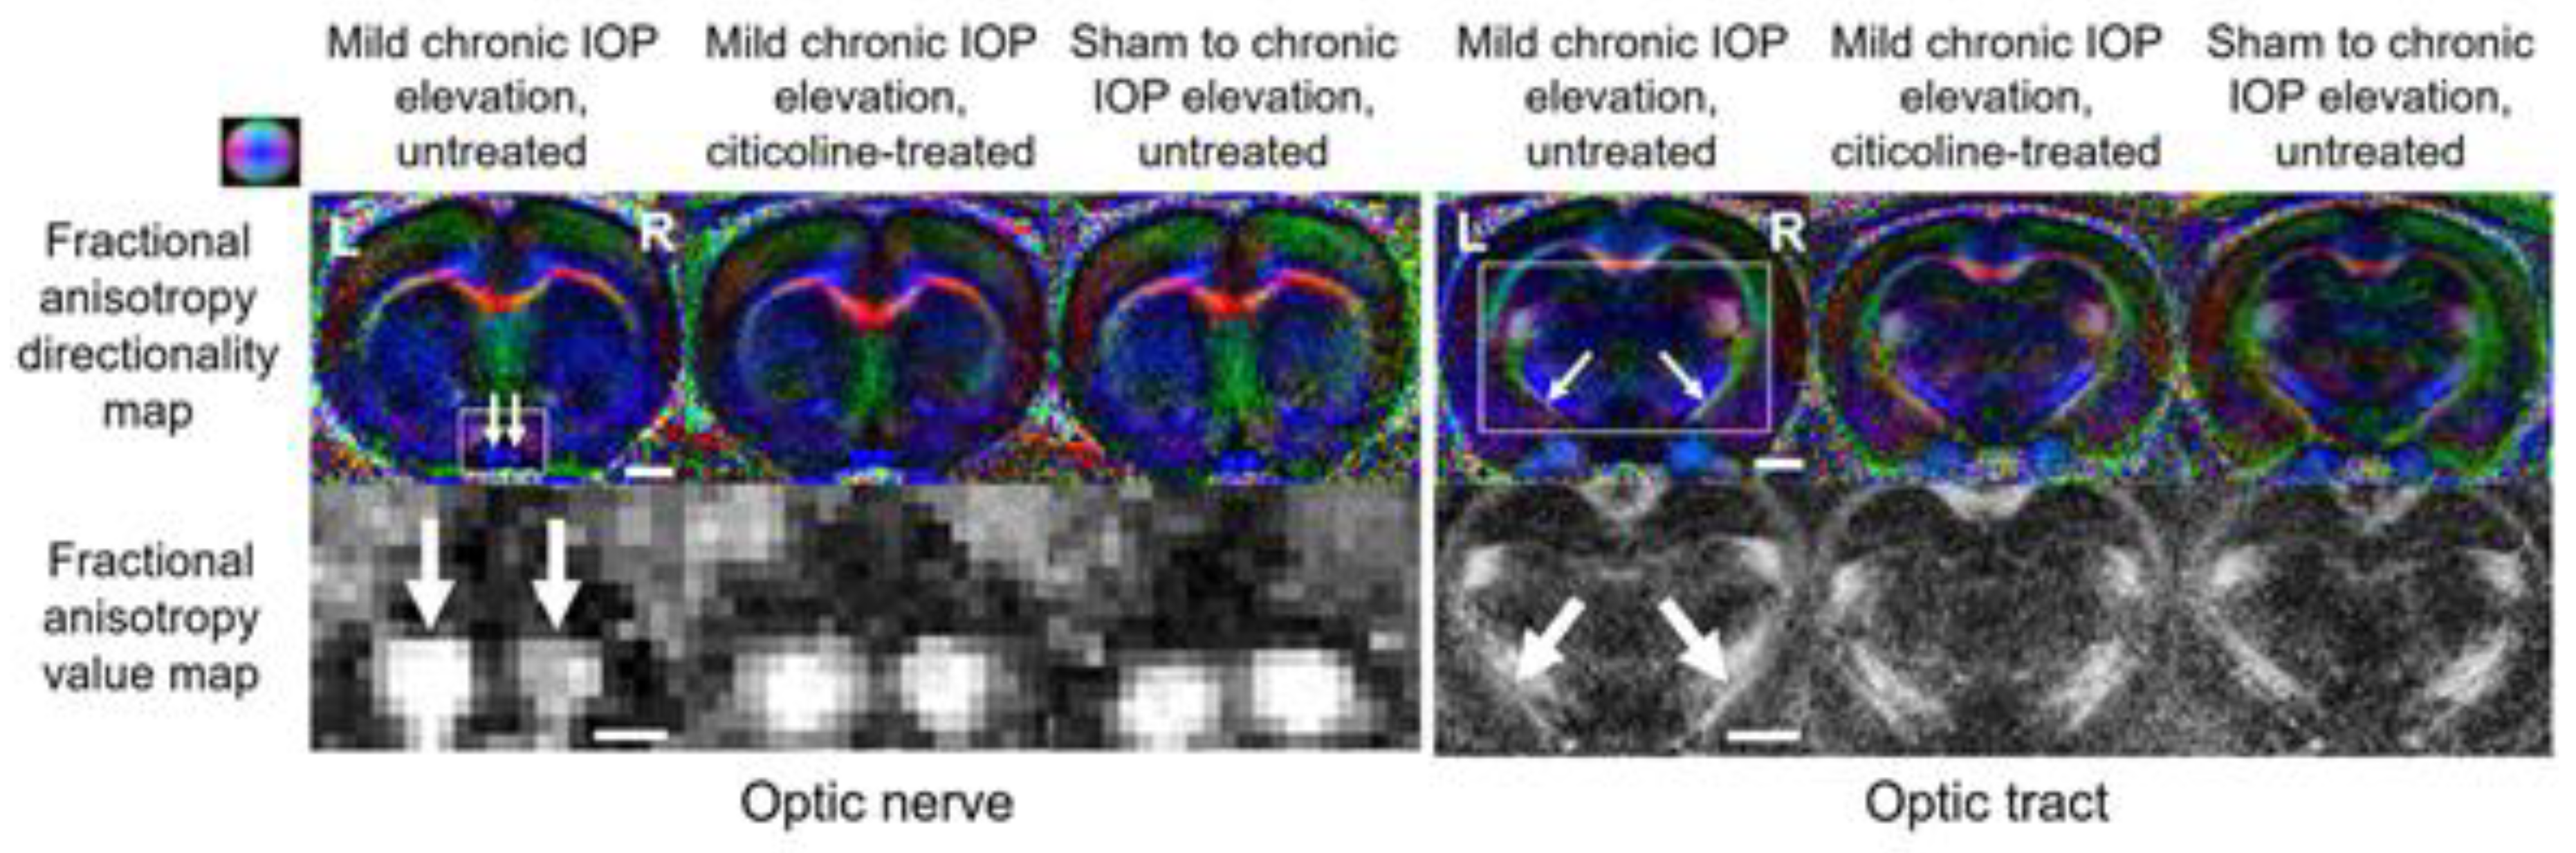

- Van der Merwe, Y.; Murphy, M.C.; Sims, J.R.; Faiq, M.A.; Yang, X.-L.; Ho, L.C.; Conner, I.P.; Yu, Y.; Leung, C.K.; Wollstein, G.; et al. Citicoline Modulates Glaucomatous Neurodegeneration Through Intraocular Pressure-Independent Control. Neurotherapeutics 2021, 18, 1339–1359. [Google Scholar] [CrossRef]

- Colbert, M.K.; Ho, L.C.; van der Merwe, Y.; Yang, X.; McLellan, G.J.; Hurley, S.A.; Field, A.S.; Yun, H.; Du, Y.; Conner, I.P.; et al. Diffusion Tensor Imaging of Visual Pathway Abnormalities in Five Glaucoma Animal Models. Investig. Opthalmol. Vis. Sci. 2021, 62, 21. [Google Scholar] [CrossRef]